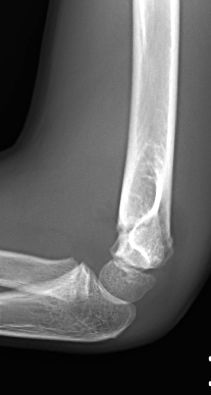

Figura 8: a-d, Imagen radiografica de fractura del cóndilo lateral con desplazamiento articular. Tratamiento quirúrgico mediante reducción abierta y osteosíntesis.